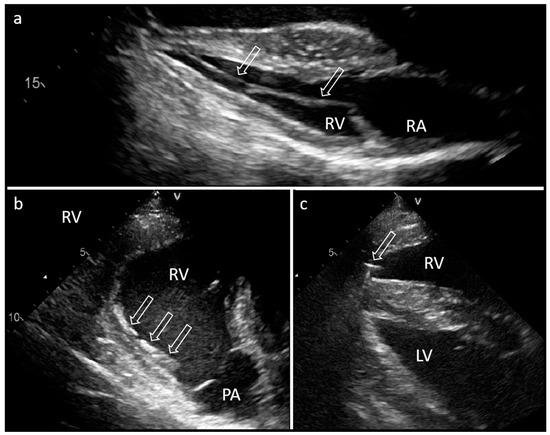

The surgical approach to the left cephalic vein was performed in the left lateral pectoral groove at the level of the shoulder joint. Following a longitudinal skin incision of 7 cm, the vein was exposed and freed from the underlying tissue by blunt–sharp dissection. Ligatures were placed around the exposed vein, but not yet tied. After phlebotomy, the electrode was inserted into the vein and advanced towards the heart. Subsequently, the electrode tip was visualized and navigated through the right atrium and into the right ventricle by echocardiographic guidance (Figure 2). The electrode tip appeared hyperechogenic with an irregular structure, which enabled the differentiation from the temporary pacing electrode. The electrode was positioned close to the apex of the right ventricular septum and connected to a programmer device (Merlin™, St. Jude Medical™, Abbott Laboratories Inc., Saint Paul, MN, USA) that measured and displayed the electrical potentials derived from the lead tip. The electrode position had to be corrected twice due to a stimulation threshold higher than 2 V or electrode displacement in the direction of the outflow tract (Figure 2).

Echocardiography 40 days and 17 months after surgery showed that the lead was in its correct position with close contact with the endocardium (Figure 2). No structural changes of the endo- or myocardium and no pericardial effusion were visible in the echocardiographic examination. Radiographs confirmed the course and location of the electrode and the pacemaker (Figure 4). Left ventricular function (ejection fraction based on Simpson’s method of discs) remained unchanged during the follow-up period. At the time of follow-up, the battery was still charged for 10 years.

Figure 2. Exemplary images of echocardiography (B mode) 17 months after implantation (a) and during electrode placement (b,c) of a pacemaker in a donkey. (a) Transducer position: left body side, 4th intercostal space. The pacing electrode (arrows) is visible inside the right ventricle and is fixed at the septum near the apex. (b) Transducer position: right body side, 4th intercostal space. Image of the displaced electrode tip (three arrows) towards the pulmonic artery (PA) during implantation. (c) The electrode tip (arrow) inside the right ventricle (RV) is visible close to the fixation screw. RA, right atrium; LV, left ventricle.